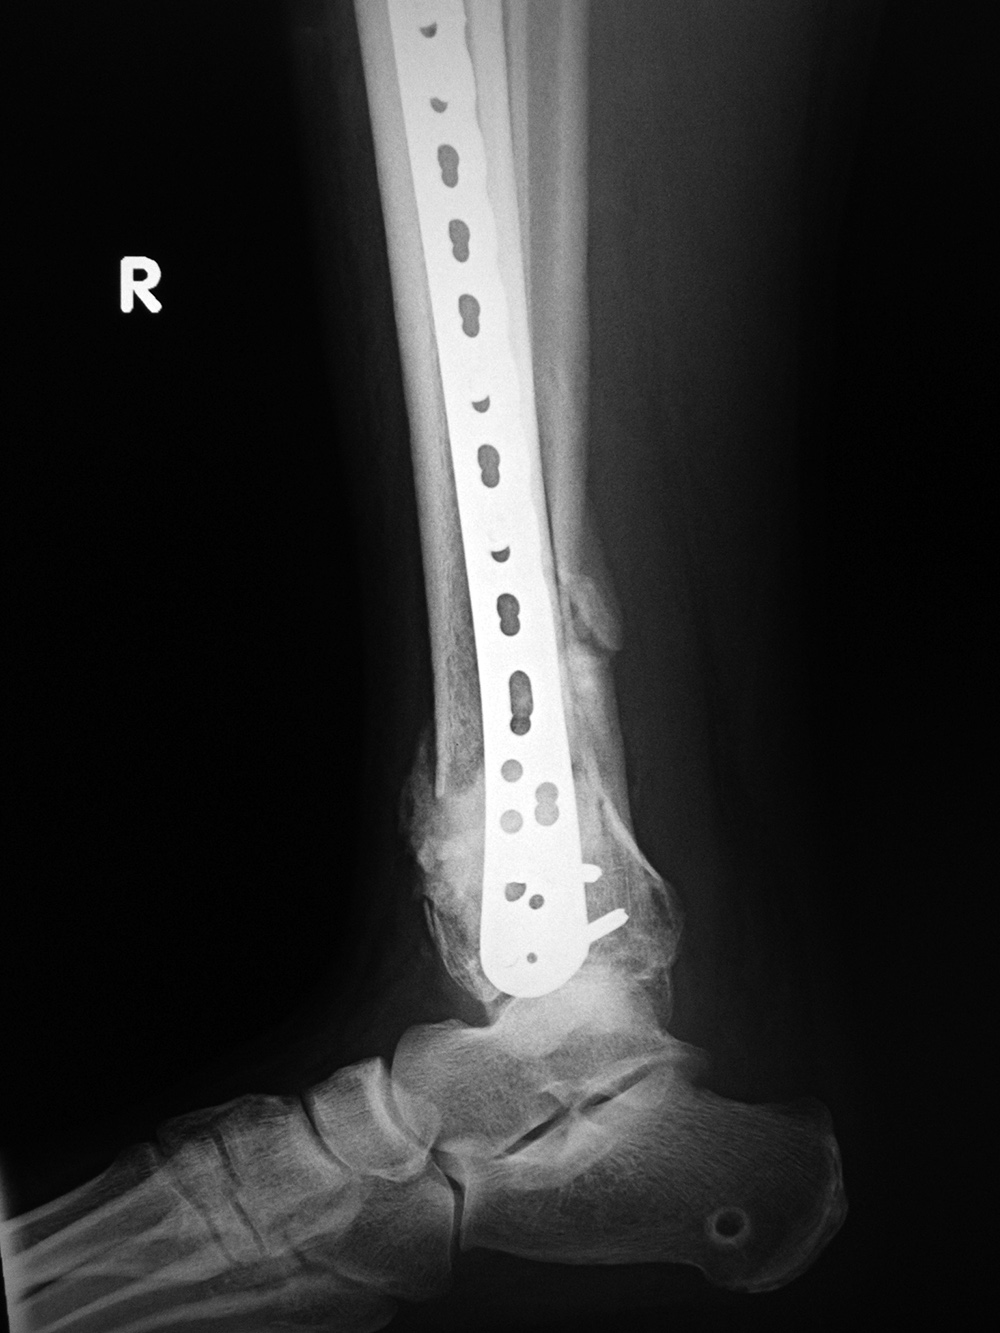

Right tibia periarticular locking plate and bone substitute

Right tibia LISS plate and bone substitute